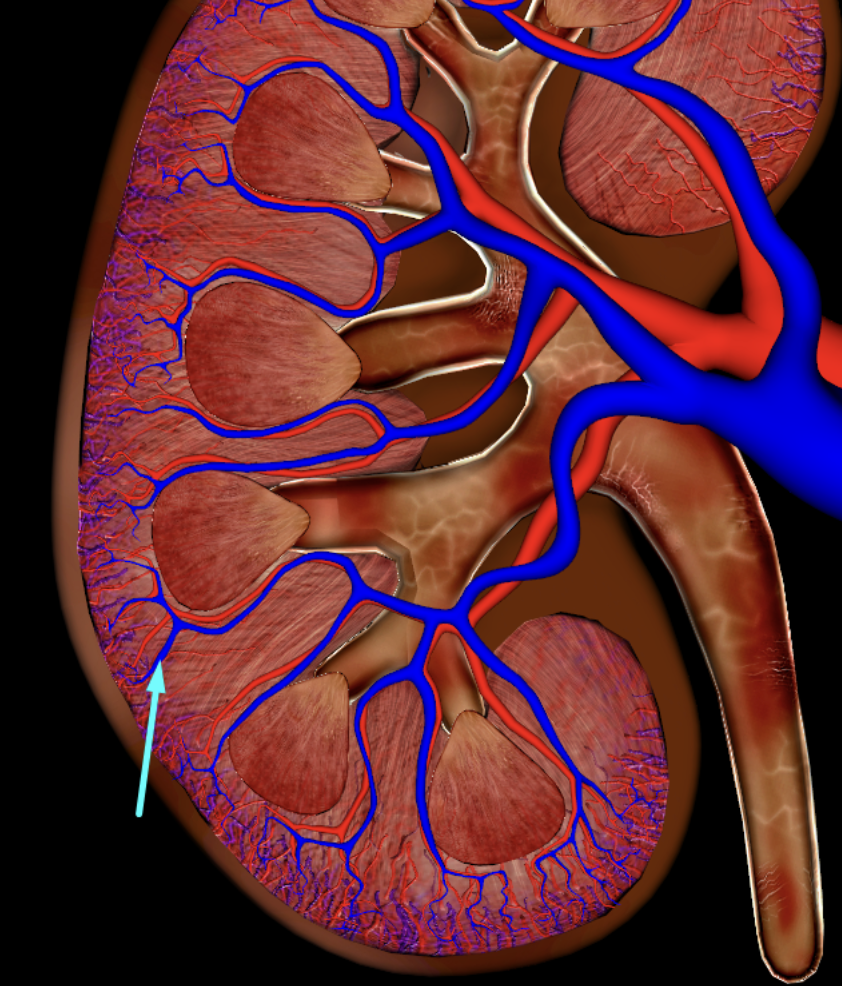

renal cortex

green

renal medulla

blue

renal columns

yellow

renal pyramids

purple

renal lobe

orange

renal papilla

minor calyx

teal

major calyces

renal pelvis

interlobular vein

segmental artery

interlobar vein

arcuate artery